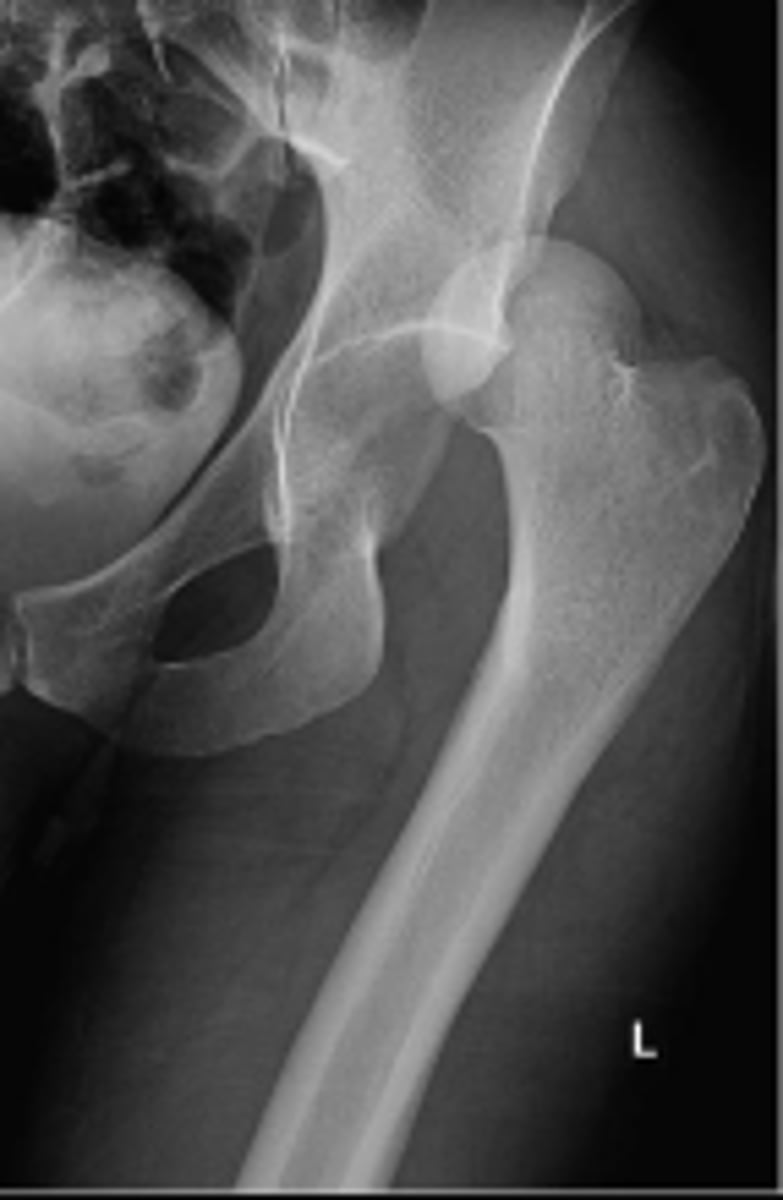

Posterior hip dislocation

What is most significant radiographic finding?

Femoral angle

What is the name of the assessment?

120-130 degrees

What is the normal range for this assessment?